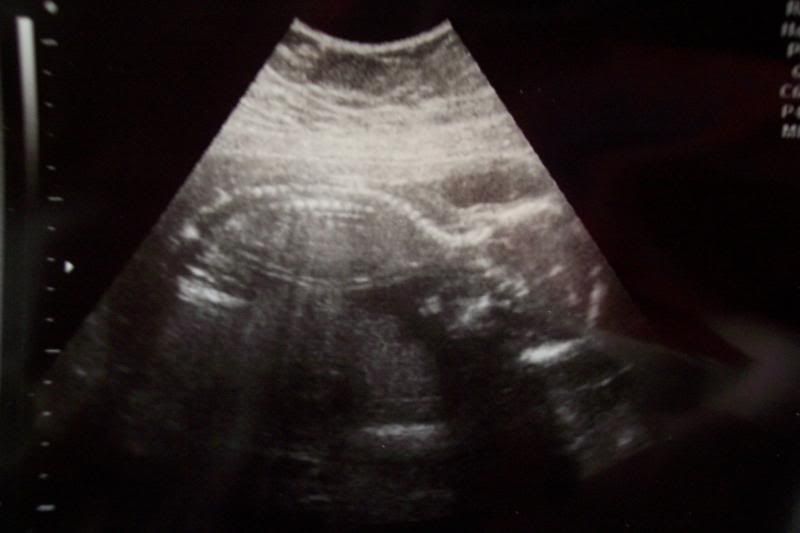

Floating on his belly like big brother did for his ultrasound!